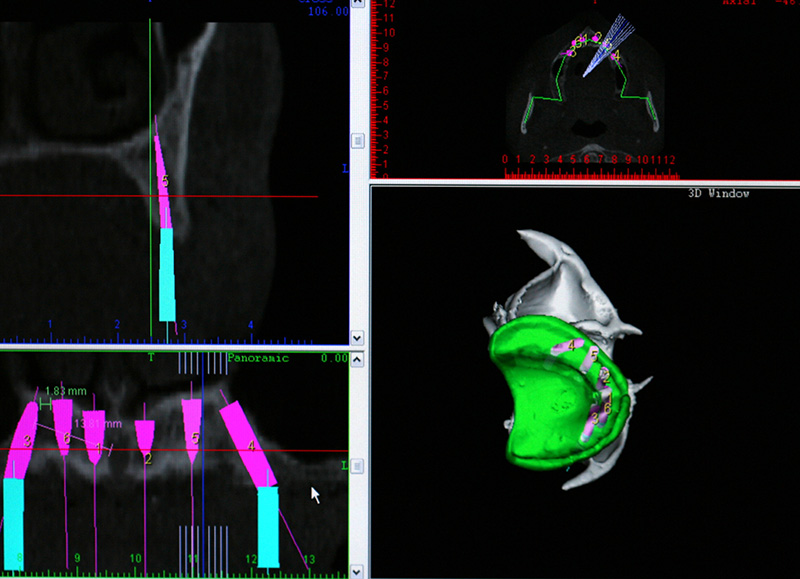

Na Clínica Pontes Odontologia, somos referência em implantes dentários em Fortaleza, oferecendo tratamentos de alta qualidade e tecnologia de ponta. Os implantes dentários são estruturas de titânio posicionadas cirurgicamente no osso maxilar ou mandibular para substituir as raízes dos dentes ausentes. Essa técnica permite a fixação de próteses personalizadas, restaurando a função mastigatória, a estética e a autoestima dos nossos pacientes.

Utilizamos a tecnologia CAD CAM, um sistema avançado que possibilita a confecção precisa das próteses dentárias diretamente sobre os implantes. Esse método inovador garante um ajuste perfeito, um resultado estético superior e proporciona muito mais conforto e durabilidade. Com o CAD CAM, nossos pacientes contam com um processo mais rápido e previsível para alcançar o sorriso desejado.